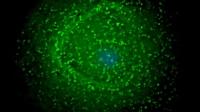

Учёные открыли уникальные иммунные клетки, способные замедлять старение

Учёные из Университета Бен-Гуриона в Негеве (Израиль) совершили открытие, раскрывающее новый механизм борьбы со старением. Исследователи обнаружили, что особый тип иммунных клеток, известный как CD4 T-клетки, способен трансформироваться и целенаправленно уничтожать так называемые сенесцентные, или «зомби»-клетки, которые накапливаются в организме с возрастом. Эти стареющие клетки, хотя и перестают делиться, остаются активными и выделяют вредные молекулы, провоцирующие хроническое воспаление и повреждение тканей, что в конечном итоге приводит к возрастным заболеваниям.